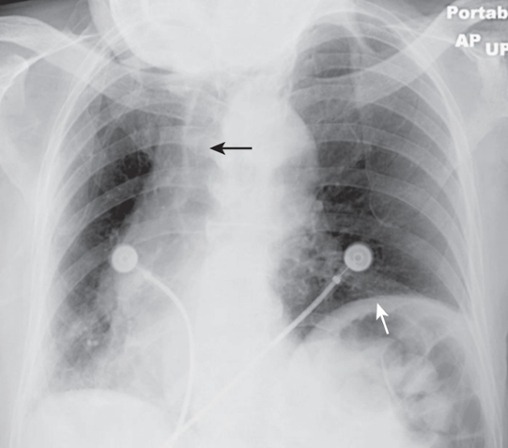

Patient markedly rotated toward her own right. Rotation can distort the appearance of the normal contours of the heart and hila.

Notice how the left hemidiaphragm, being farther from the cassette than the right hemidiaphragm because of the rotation, appears higher than it normally would (white arrow).

The hilum could also appear larger than its actual size because of rotation. The heart and the trachea (black arrow) appear displaced into the right hemithorax because of the rotation.